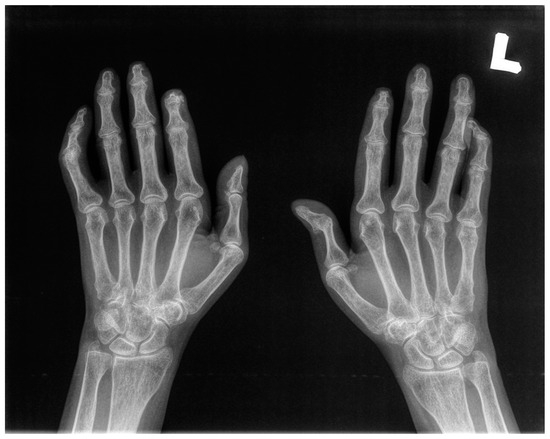

2.3. Radiological (X-ray) Evaluation